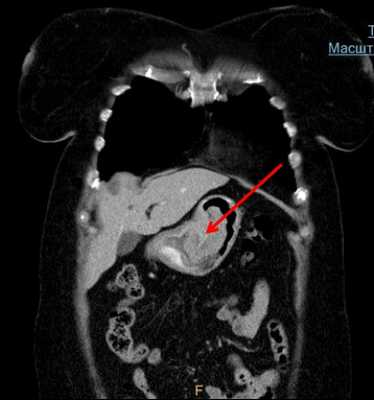

Мультиспиральная компьютерная томография (МСКТ) с внутривенным контрастированием является обязательным методом диагностики рака пищевода. Необходимо выполнять МСКТ как органов грудной клетки, так и брюшной полости. МСКТ обязательно надо выполнять с внутривенным введением контрастного вещества, так как опухоль и лимфатические узлы накапливают рентгеноконтрастный радиофармпрепарат. Проведение исследования без контрастного вещества не информативно. Мультиспиральная компьютерная томография позволяет определить точные верхние и нижние границы опухоли, глубину прорастания опухоли в стенку пищевода, распространение опухоли на соседние органы и структуры. Так же по результатам исследования можно сделать выводы о наличии поражения регионарных лимфатических узлов (наличие метастазов), а так же о вторичном распространении (метастазировании) опухоли в органы мишени (печень, легкие, кости скелета и др.). Результаты МСКТ принципиально важны для правильного стадирования опухолевого процесса и определения дальнейшей тактики лечения, решения вопроса о возможности выполнения радикального хирургического вмешательства.